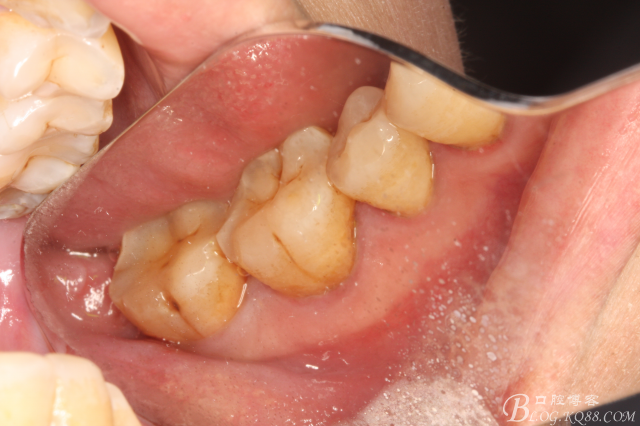

圖1. 口內(nèi)38完全埋伏